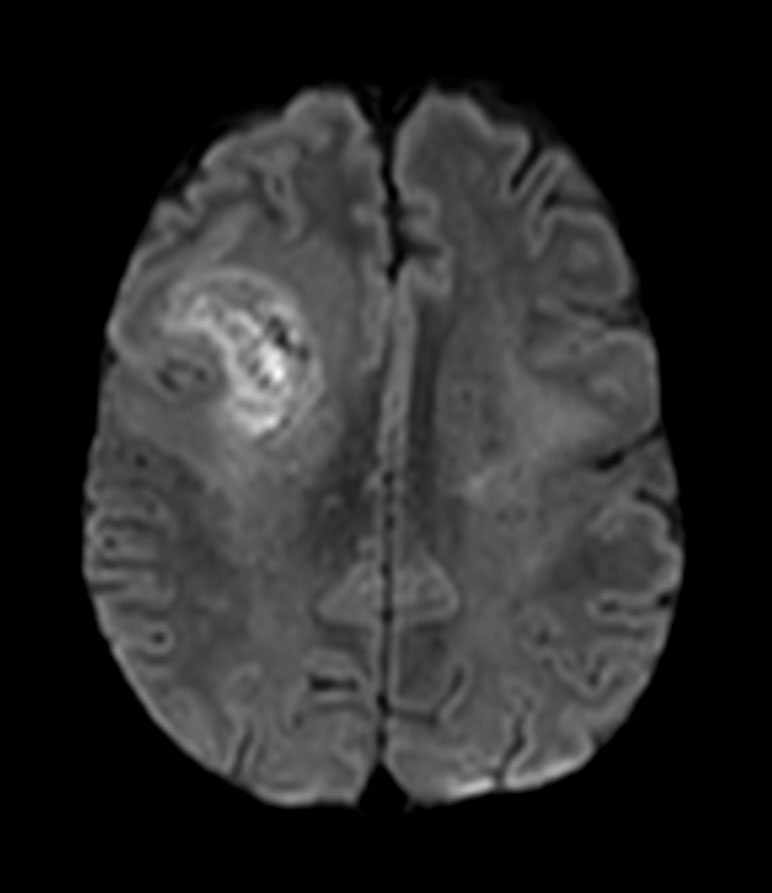

Axial DWI (b1000)